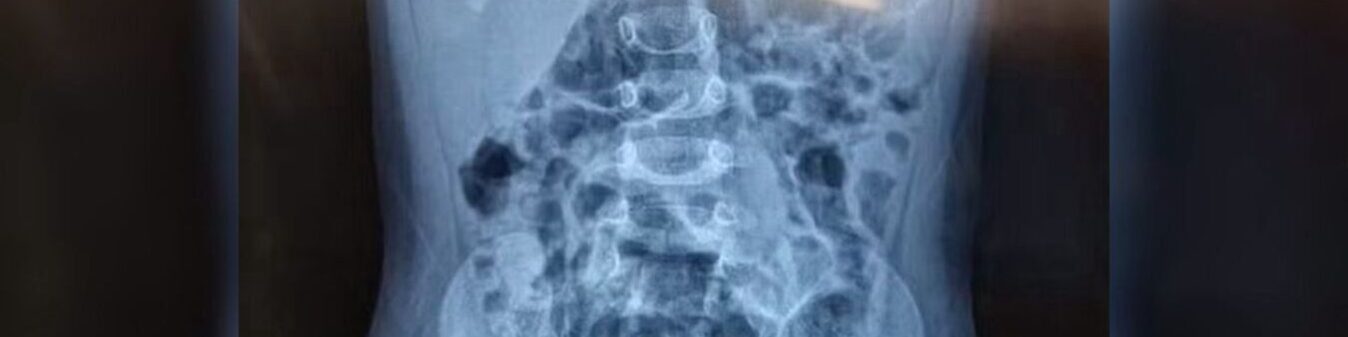

Elas foram encaminhadas para o hospital e, após a realização dos exames, um raio-X apontou a presença de objetos estranhos dentro do corpo da menina. Ela também tinha lesões nas partes íntimas.